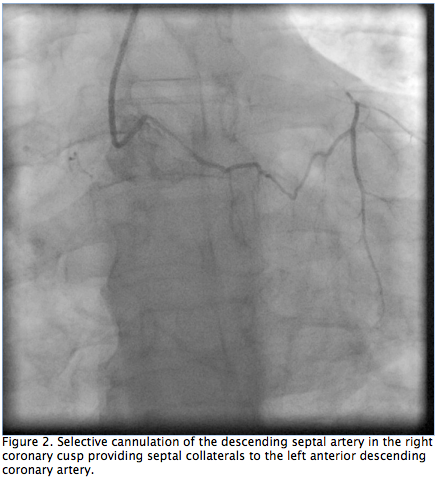

Figure 2. Selective cannulation of the descending septal artery in the right coronary cusp providing septal collaterals to the left anterior descending coronary artery (click thumbnail to view larger image).

There were two collateral systems supplying the LAD. These were: (1) the DSA originating from the right coronary cusp giving collaterals to the septal branch and filling the LAD to the apex (Figures 2 and 3); and (2) collaterals from the conus branch of the RCA reaching the first septal branch of the LAD (Figures 3 and 4). Both collateral systems were small in size. The dominant RCA had a focal segment of 60%-70% stenosis (Figure 4). Left ventricular systolic function was normal. The left circumflex (LCX) had mild disease. The patient underwent successful bypass surgery with grafts to the LAD as well as RCA and had uneventful recovery.

In a postmortem angiographic study, Rodriguez et al3 described an accessory artery that helped supply the cardiac interventricular septum in 12% of human hearts and up to 66% of the hearts in other animal species. The described artery originates close to the right coronary orifice, descends through the superior septal border, and ramifies in the interventricular septum. The vessel was referred to as the “descending septal artery.” The DSA was described as arising from the first centimeter of the RCA, from a common orifice with the RCA, a common orifice with the conus branch, or from an independent ostium in the right coronary cusp. The DSA was two times more likely to be present if there was coronary artery occlusion. The authors concluded that this branch is more likely to be a potential source of collateral circulation, and the artery has not gained the attention it deserves. Our patient had severe occlusive coronary artery disease with preserved left ventricular function. Another postmortem stereoscopic radiography study4 performed to understand the blood supply of the conduction system described the descending septal branch as supplying the proximal conduction system in 68% of human hearts studied. The author studied 112 human hearts and half of the patients with the descending septal branch had severe coronary disease. The descending septal branches arose directly from the RCA, from the first conal branch of the RCA, or from a separate aortic ostium in 58%, 25%, and 16.7% of the patients, respectively. Anastomosis was observed between the DSA and septal branches of the LAD artery in hearts with severe coronary artery disease. Our patient’s angiography revealed a significant collateral circulation to an occluded LAD from the DSA (Figures 2 and 3). Failure to identify the target on the LAD might have compromised the treatment of our patient.